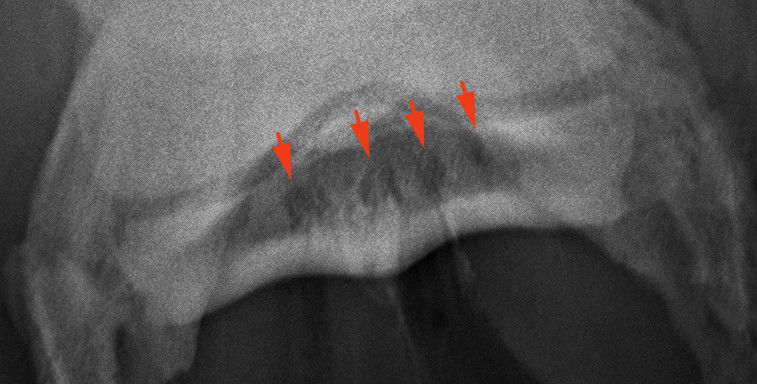

A másik nyírcsont felvétel, a skyline. Úgy készül, hogy a lovat ráléptetjük a kazettára. A nyilak mutatják a csont helyeződését.

Kitágult csatornák (vékony nyilak) és oldódás a csont kéregállomáányában 8 vastag nyíl).